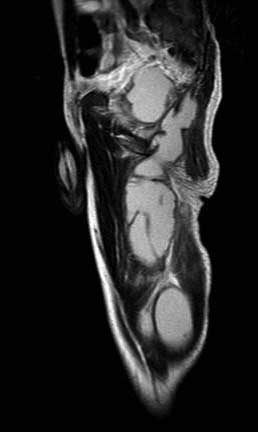

[Ortho] Остеомиелит таза?

Пункцию взяли - гной, роста нет, микроскопия ничего не нашла. Какие будут соображения? Что и

откуда натекло? Pubic rami? Анус? Чаще бывает Iliopsoas абсцесс, насколько знаю.

Имя     : mri 51201644.jpg